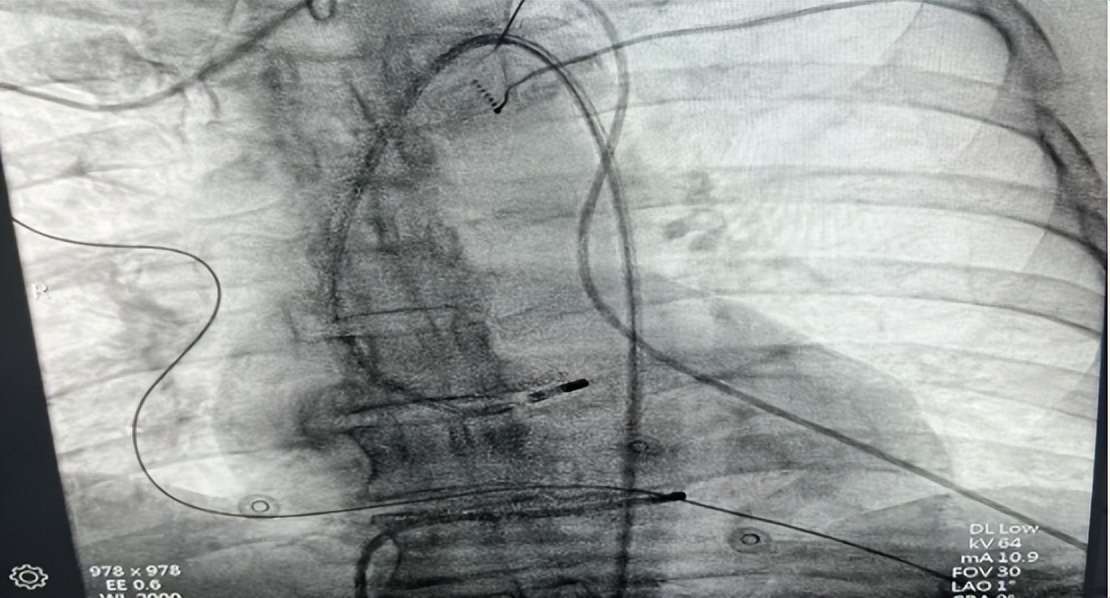

△术中导管放置

“就像用精准导弹打掉靶点!”随着射频电流释放,异常病灶被彻底消融。整个手术仅用1小时,创口只有米粒大小。术后第三天,夏先生就康复出院,心悸症状完全消失。